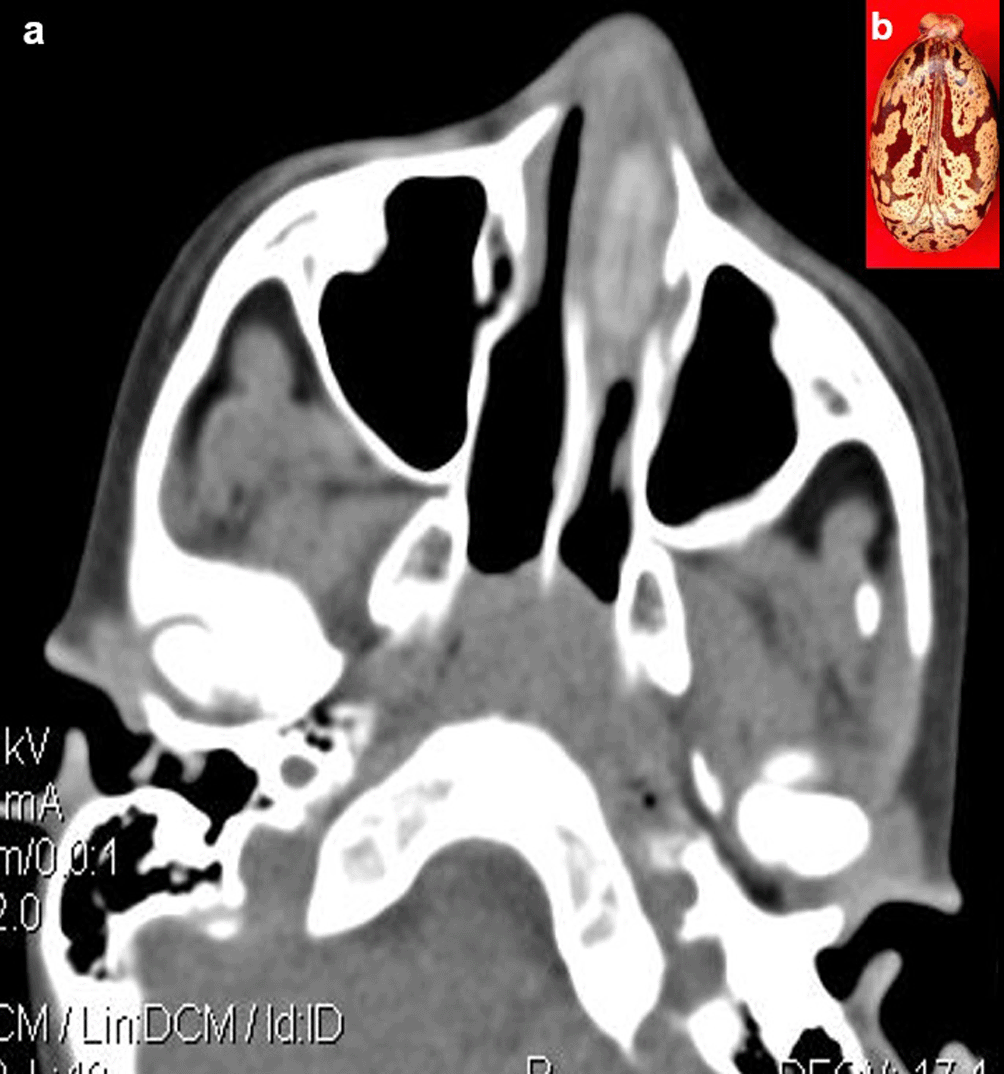

Case 5: A seven-year-old boy came with a history of epistaxis for a day. On clinical examination, foul-smelling, blood-tinted nasal discharge was noted on the left side. Further examination was not possible as the child was uncooperative. CT paranasal sinuses (PNS) revealed a non-enhancing hyperdense lesion in the left nasal cavity, possibly a foreign body. It was removed under anaesthesia and found to be a castor seed.

When a patient cannot provide a sufficient history or has swallowed things that are not naturally radio-opaque, the diagnosis of an ingested foreign body is frequently missed. If a foreign body is suspected and is not visible on a Radiograph because of its radiolucent nature, a CT scan of the abdomen or chest may be beneficial8 (Figure 4a,b).